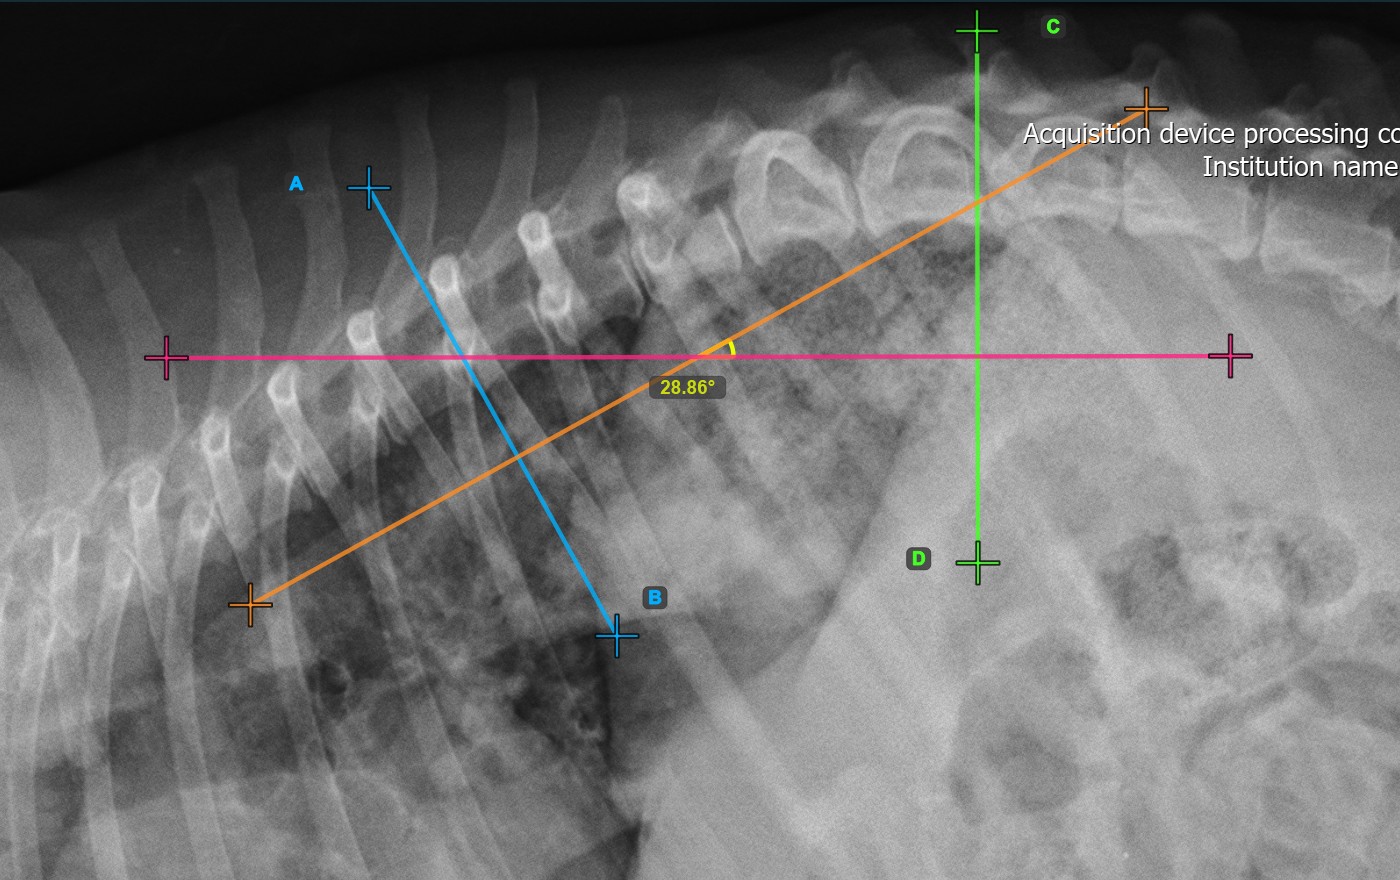

Markieren Sie die zweite Wirbellinie an der Wirbelsäule, um die Deformität zu berechnen.

Identifizieren Sie die Wirbelendplatte am gegenüberliegenden Ende der größten Wirbelsäulenkrümmung. Platzieren Sie den Start- und Endpunkt der zweiten Wirbellinie genau entlang der identifizierten Endplatte. Passen Sie bei Bedarf jeden Punkt in der Szene an, um die Linie besser an die Endplatte auszurichten.

Die Cobb-Winkelmessung wird automatisch berechnet und abgeschlossen, sobald die beiden Wirbellinien platziert sind. Sie zeigt den Winkel der Wirbelsäulenkrümmung in Grad an.

Das untenstehende Bild zeigt eine typische Platzierung der zweiten Wirbellinie.

Ändern Sie die Position und Ausrichtung der beiden Wirbellinien, um den Cobb-Winkel automatisch neu zu berechnen.